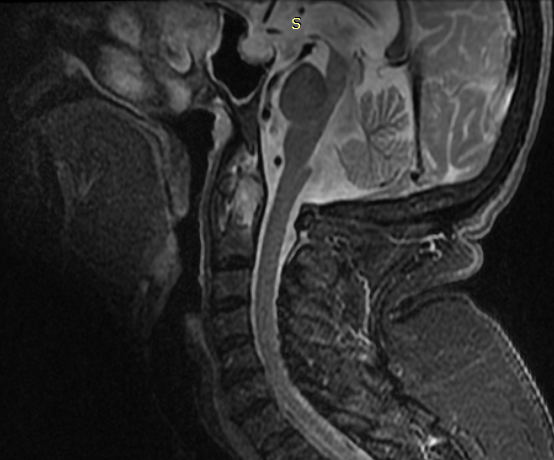

NSAIDs treatment was started with diclofenac 150 mg daily with no clinical response and then with meloxicam 15 mg daily with marginal pain relief. A magnetic resonance imaging (MRI) with T2-STIR sequence of the cervical tract was performed, which showed high hyperintensity signal of the odontoid process and thickening of soft tissue around the atlanto-epistrophic joint, indicating bone edema of the dens and associated synovitis (Figure 1).

Figure 1: MRI of the cervical spine with sagittal acquisition at first evaluation. STIR sequences show high intensity signal of the odontoid process (arrow) and of the transverse ligament complex (arrow head) detecting bone marrow edema of the dens and of surrounding ligaments.